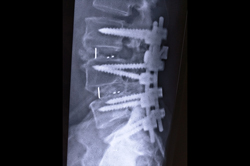

Spine